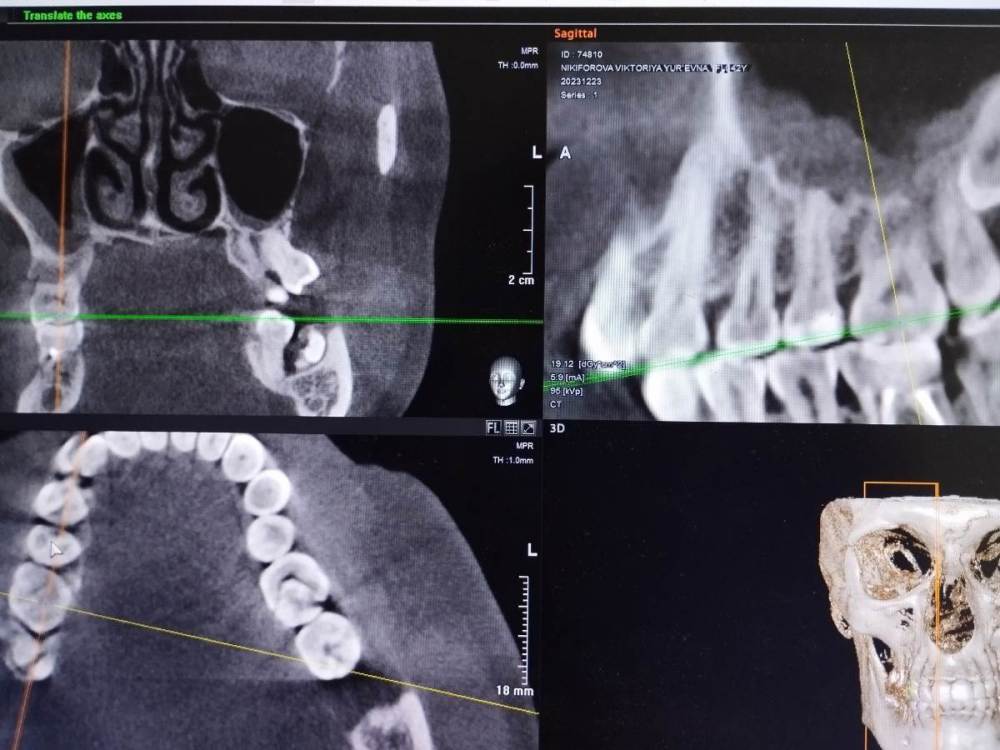

Подскажите, действительно ли над 5-ым верхним зубом киста?

Здравствуйте! Врач говорит, что нужно лечить каналы зуба. Зуб под пломбой более 10 лет. Не беспокоит. Доктор прав?

Здравствуйте. Похоже, что да. Но фото размытые (потому что сфотографированы прямо с экрана. Лучше делать скриншоты, а ещё лучше выложить КТ целиком) и плохо понятно.